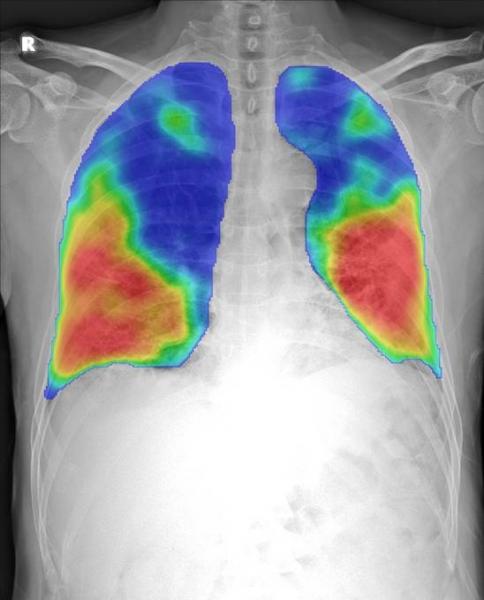

Dutch Companies Offer Free Innovative Covid 19 Ai Software Imaging Technology News